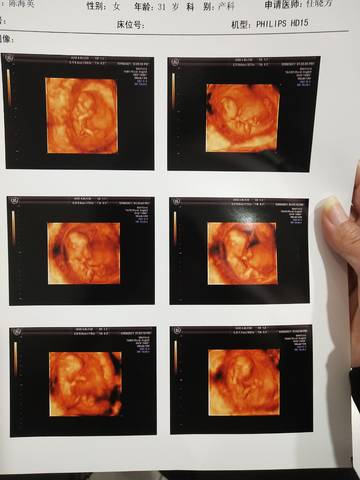

今天做了NT,一切正常!好奇是女儿还是儿子

摘星星的奇 2021-12-09 19:30

你好。我们是判断不了男宝宝跟女宝宝的,孕期定期检查,我觉得宝宝健康就好的。祝心想事成 。

一般四维得时候看着比较准

你好亲爱的,通过这个来判断男孩女孩是不太准确的哈。那么这个男孩女孩都是我们最爱的宝贝哈,我们要给他同等的关爱和呵护,也祝你可以如愿以偿,心想事成,祝你好运。